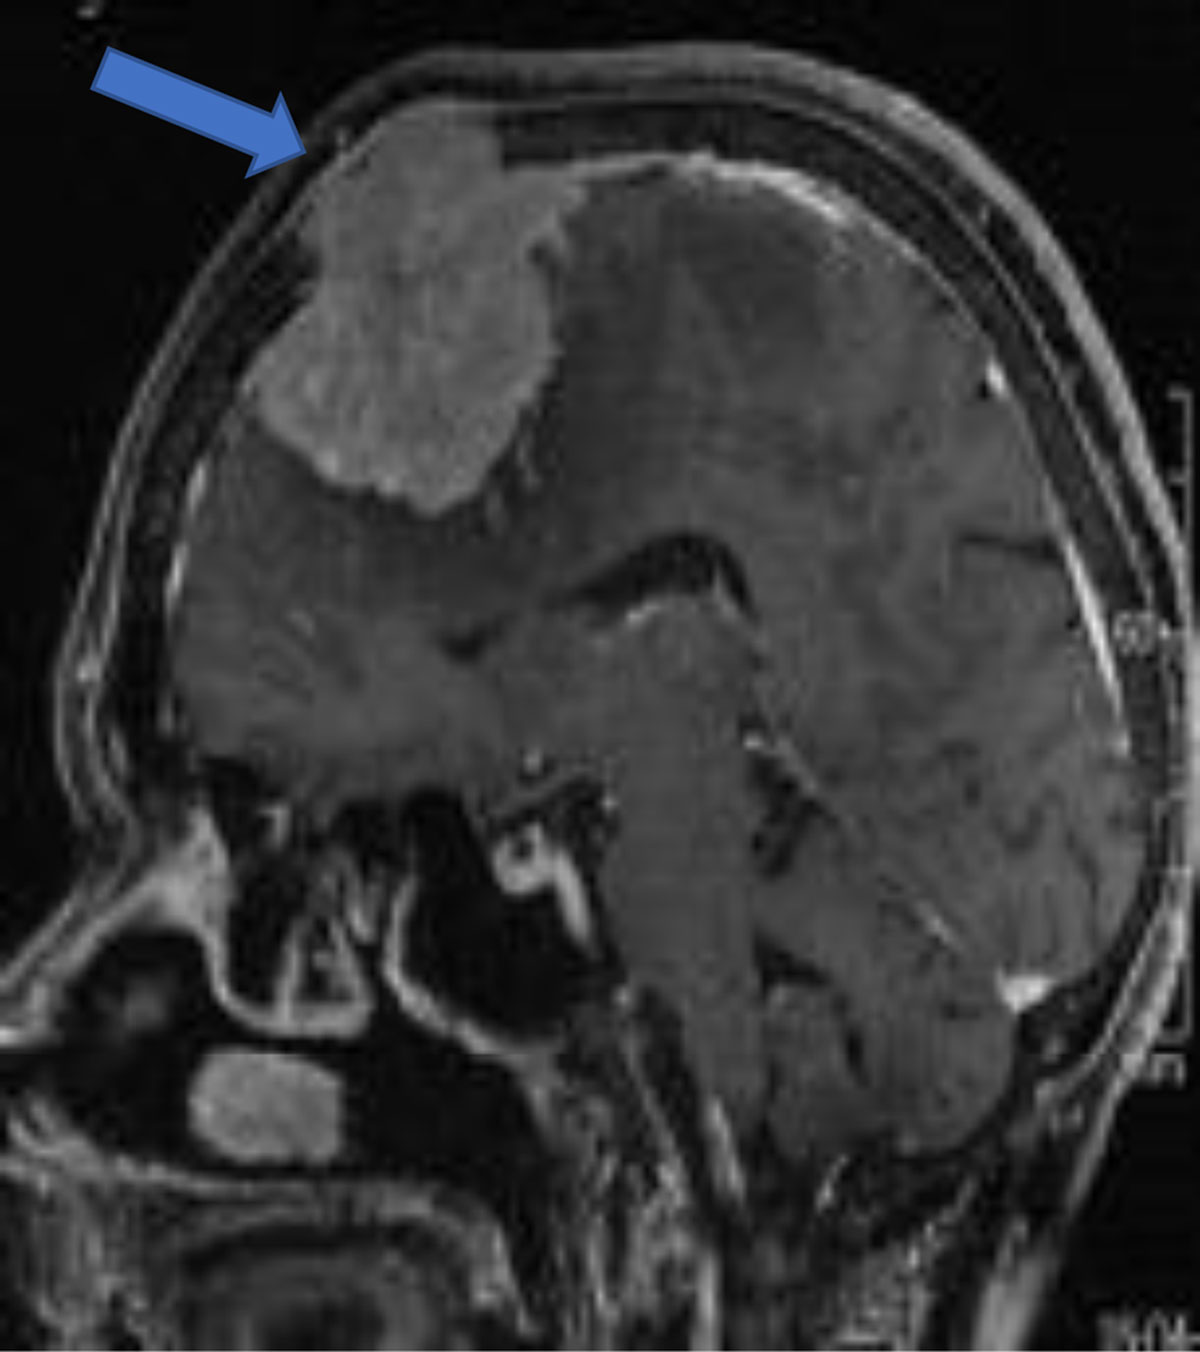

Bony involvement occurs with benign and malignant tumors [8] (Figure 10).

Figure 10

Sagittal post-contrast convexity meningioma with osseous invasion (arrow).

Sinus invasion is the invasion of venous sinuses and is a known complication [2] (Figures 10, 11).